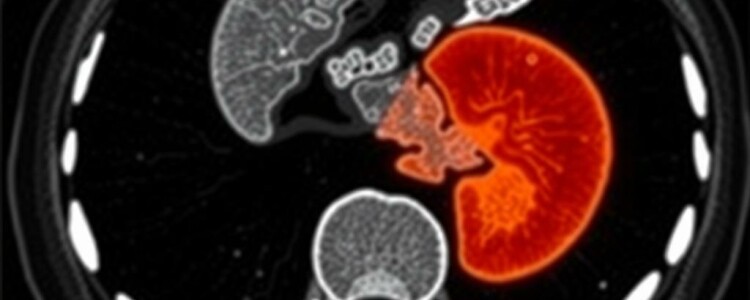

Además, la apendicitis presenta una gama de manifestaciones radiológicas relativamente constantes —engrosamiento mural apendicular, dilatación, realce tras contraste, inflamación periapendicular, presencia de líquido o absceso— lo que hace posible que modelos de aprendizaje automático aprendan patrones útiles a partir de suficientes ejemplos. Por eso este ámbito se ha convertido en un laboratori o real para aplicar algoritmos de visión por computador y de aprendizaje profundo en imágenes médicas.

Las redes convolucionales (CNN) son las arquitecturas dominantes para imágenes: aprenden características directamente de los píxeles y pueden distinguir texturas, bordes y patrones complejos. Modelos más avanzados combinan CNN con enfoques de atención para centrar el análisis en regiones relevantes o usan redes 3D que procesan volúmenes completos de TC para conservar información espacial. Otra estrategia complementaria es la radiómica, que extrae cientos de características cuantitativas de las imágenes (formas, texturas, intensidad) y las usa en modelos estadísticos o máquinas de soporte vectorial. En la práctica clínica emergente, lo habitual es ver soluciones híbridas que combinan segmentación automática del apéndice, extracción radiómica y clasificación con redes profundas.

Un flujo típico de IA integrado en el proceso de lectura tomográfica puede incluir los siguientes pasos: preprocesado de la imagen (normalización, eliminación de artefactos), detección automática de la región abdominal relevante, segmentación del apéndice, cálculo de métricas (diámetro, grosor de pared, realce), evaluación de signos periapendiculares y, finalmente, una clasificación probabilística que sugiere la presencia o ausencia de apendicitis y su posible complicación. Este resultado se presenta al radiólogo dentro del visor de imágenes, enfatizando hallazgos y proponiendo métricas que el clínico puede revisar y aceptar o refutar.